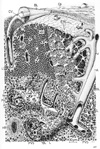

毛細管;毛細血管【もうさいけっかん;もうさいかん】 (毛細血管は、細動脈と細静脈の間にあって、多くの分枝、吻合を繰り返し、組織中を網目状に走行する、非常に細い血管である。その直径は8~10μmで、赤血球より幾分大きい程度である。毛細血管壁は内腔をつつむ1~3個の内皮細胞と、その外側にまばらに分布する周皮細胞とから構成されている。細動脈から毛細血管への移行は、中膜における平滑筋細胞の有無により、はっきりと区別されるが、毛細血管から細静脈への移行は徐々に生じ、両者を明確に区別することは困難である。多くの分枝吻合により、毛細血管網における血管表面積は、非常な増大を示す。表面積の増大とともに、血流に対する抵抗も大となり、血液はこの部位を、非常にゆっくり流れることになる。大動脈では血液は、平均320mm/sで流れるのに対し、毛細血管ではその約1/1000程度の速さでしかない。血液はゆっくりと流れながら、増大した血管内腔面に十分ふれ、薄い血管壁を介して、十分な物質交換を行うことになる。毛細血管壁の構造は、光顕による観察から、すべて同じと考えられていたが、電顕的には、主として内皮細胞の違いから、さらに3つに分けられることがわかった。それらは、連続型毛細血管、有窓型毛細血管、洞様毛細血管である。①連続型毛細血管continuous capillaryは最も普通にみられる毛細血管である。筋肉や結合組織、脳など、体の多くの部位に分布する。内皮細胞の核は核の部位でのみ厚く、その周囲は、連続した薄い細胞質よりなる。その厚さは通常0.1~0.2μm程度である。細胞質には細胞膜の陥入や、これらが中へ落ち込んで生じたと思われ60~70nm径の小胞がほとんどみられないものもある。血管壁の浸透性と関係があるようである。細胞と細胞の連結部では、細胞膜は一定の間隙を隔てて、まっすぐに、あるいはジグザグにかみ合っている。内腔側には閉鎖結合もみられる。またこの連結部には、内腔に向かって突出する、内皮細胞のヒダが時に観察される。これは辺縁ヒダmarginal foldとよばれるが、その機能については明確でない。基底膜は、内皮細胞の外側を完全におおっている。②有窓型毛細血管fenestrated capillaryは、内皮細胞の核部以外の、周囲に伸びる細胞質は連続型のものよりもっと薄く、かつ、その部位に、直径60~80nm程度の多くの孔が存在する。時にはもっと大きな径を示すものもある。腎臓、内分泌腺、超粘膜など、物質透過の盛んな部位に多く見られる。腎糸球体における毛細血管では、孔は、血管腔側と基底側の間を完全に通過するが、普通は、孔の途中に非常に薄い1層の隔膜が横切り、孔を閉ざしている。この隔膜の性質および機能については明らかでない。物質透過の際のフィルターの役割を果たしているのかも知れない。孔は、一定間隔に規則正しく配列するが、内皮細胞全体に一様に分布するのではなく、幾分細胞質の厚い、全く孔の存在しない部位が帯状に伸び、細胞表面を幾つかに区切っている。孔の分布の状態、数は組織により多様である。内皮細胞の外側にある基底膜は、連続型の場合と同様、孔に関係なく全体をつつむ。③洞様毛細血管は類洞ともよばれ、内皮細胞は器官を作る実質細胞に沿うようにして並び、したがって、その横断像は必ずしもまるくなく、不規則な形を示す。太さは多様であるが、他の型の毛細血管に比べ、かなり広い管腔をもち、その中を血液は、ゆっくりと流れることができる。内皮細胞には、その細胞質を貫通する、かなり大きな孔を有するものや、かなり開いた細胞間隙を示すものがあって、それらの部位を、巨大な物質も容易に通過することができる。基底膜はあまり発達せず、不連続な物やあるいは全く欠くもものもある。洞様毛細血管は、肝臓、脾臓、骨髄などでしられるが、内皮細胞は、各組織に固有の形態を示す。④毛細血管の透過性と構造との関係は毛細血管およびこれにつづく細静脈は、血管壁を通して、血液と組織の間で物質交換を行う部位である。心臓から毛細血管に至るまでの動脈、そして心臓へと戻る静脈は、いわば血液の通路であり、毛細血管網および細静脈の領域において初めて、血液循環の本質的な機能が含まれることになる。毛細血管では、内腔表面積は非常に増大し、総表面積が6,000m2、横断面績の総和は、大動脈のほぼ800倍にも相当するという。血液はこの広い内宮面にふれながら、うすい内皮細胞と、基底膜を通して、物質の交換を行うことになる。水や電解質など低分子物質は、これらの部位を静水圧や浸透圧、濃度勾配の差によって、自由に通過しうるが、これだけでは、組織を維持するのに十分とはいえない。蛋白質のような高分子物質は、直接膜を通過することはできず、これらが膜を通過するためには、特殊な機構が必要である。)